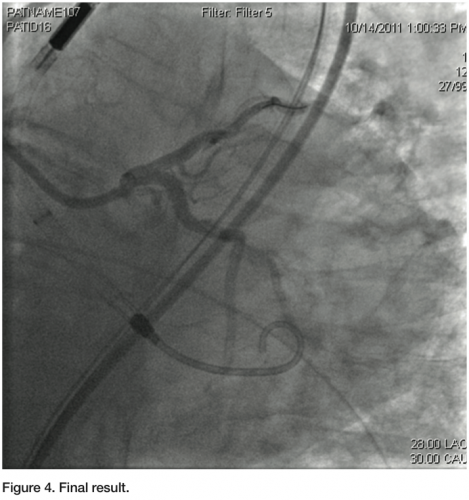

a Judkins left 3.5 guiding catheter was used to engage the left main. Two 0.014” angioplasty wires were introduced; one into the LAD, and one into the distal Cx. A 3.0 x 12 mm balloon was placed in the ostium of the Cx, and a diagnostic angiogram was obtained (Figure 1). Subsequently, a 2.5 mm balloon was placed from the left main into the LAD. A 3.5 x 8 mm bare-metal stent was placed in the proximal Cx. The 2.5 mm balloon was inflated to 10 atmospheres, protecting the left main and proximal LAD from plaque shifting during deployment of the Cx stent (Figure 2). The stent in the Cx was then withdrawn until it indented the left main balloon. The balloon in the left main was inflated for nearly a minute during this process, and the patient was completely asymptomatic. Systolic blood pressure did drop from about 130 mmHg to about 90 mmHg, but diastolic pressure was maintained due to support from the Impella 2.5 circulatory support device. Both balloons were then simultaneously inflated for about 25 seconds (Figure 3). The patient transiently developed global ST elevation and systolic hypotension, but remained asymptomatic. After both balloons were deflated, final images revealed excellent coverage of the ostial Cx lesion, with no significant compromise of the left main and LAD. Intravascular ultrasound (IVUS) analysis after stent deployment revealed a cross sectional area of 6.3 mm2 in the ostium of the LAD, with excellent visualization of the Cx stent in the ostium. At the conclusion of the procedure, the Impella 2.5 circulatory device was weaned off in the cath lab, and the 13 French sheath was removed, with the pre-placed sutures securing hemostasis. The right femoral sheath was also secured using a single Perclose Proglide device. The patient was uneventfully discharged home the following morning.

Treatment of high risk, complex coronary lesions has become feasible to perform in a safe manner with the use of percutaneous ventricular assist devices. Traditional thinking has taught us that high-risk patients benefiting from percutaneous assist devices include those with suppressed LVEF, multivessel/left main disease, or a combination of the two.6 Complete revascularization, performed without the pressure of having to operate in a hasty fashion, has clearly shown to reduce the incidence of subsequent clinical events, as evidenced by the PROTECT II trial.2 Patient subsets who may not be considered high risk due to the absence of a low LV ejection fraction or multivessel disease may still pose a high risk for hemodynamic compromise due to the amount of myocardium potentially in jeopardy when performing percutaneous intervention. The case described herein is an excellent example of a patient who had a reasonable LVEF and single vessel disease, but who was felt to be high risk. Performing revascularization in a manner allowing for the precise positioning of a stent at a critical location meant putting myocardium in potential jeopardy. The patient’s hemodynamic parameters during dual balloon inflation confirmed the hemodynamic compromise to which he was subject, but it was tolerated without any untoward effects, due to support from the Impella 2.5 circulatory assist device. It is possible future studies may show clinical benefit in this patient subset. Coupled with the ease of use of the Impella 2.5 circulatory device, indications for use of circulatory support devices in the setting of percutaneous coronary interventions may expand accordingly.